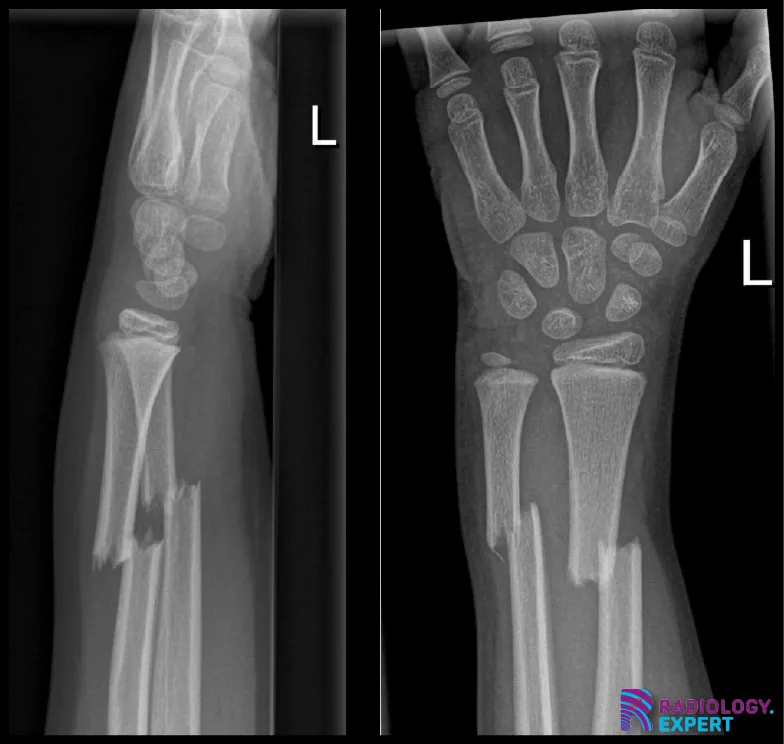

Figuur 1. Laterale en anterior-posterior opname van de linker onderarm/pols. Een kind (9 jaar oud) met distale radiusschacht & ulnaschacht fractuur. Beide tonen een dorso-ulnaire dislocatie over circa een schachtbreedte.